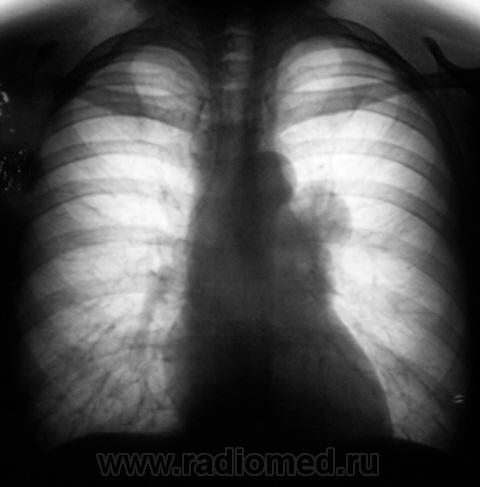

Две "флюшки"...

Слева флюорограмма за 2009 год, справа - сегодня...

Сравните флюшку за 2009г. и за 2010г. Вверху они рядом.